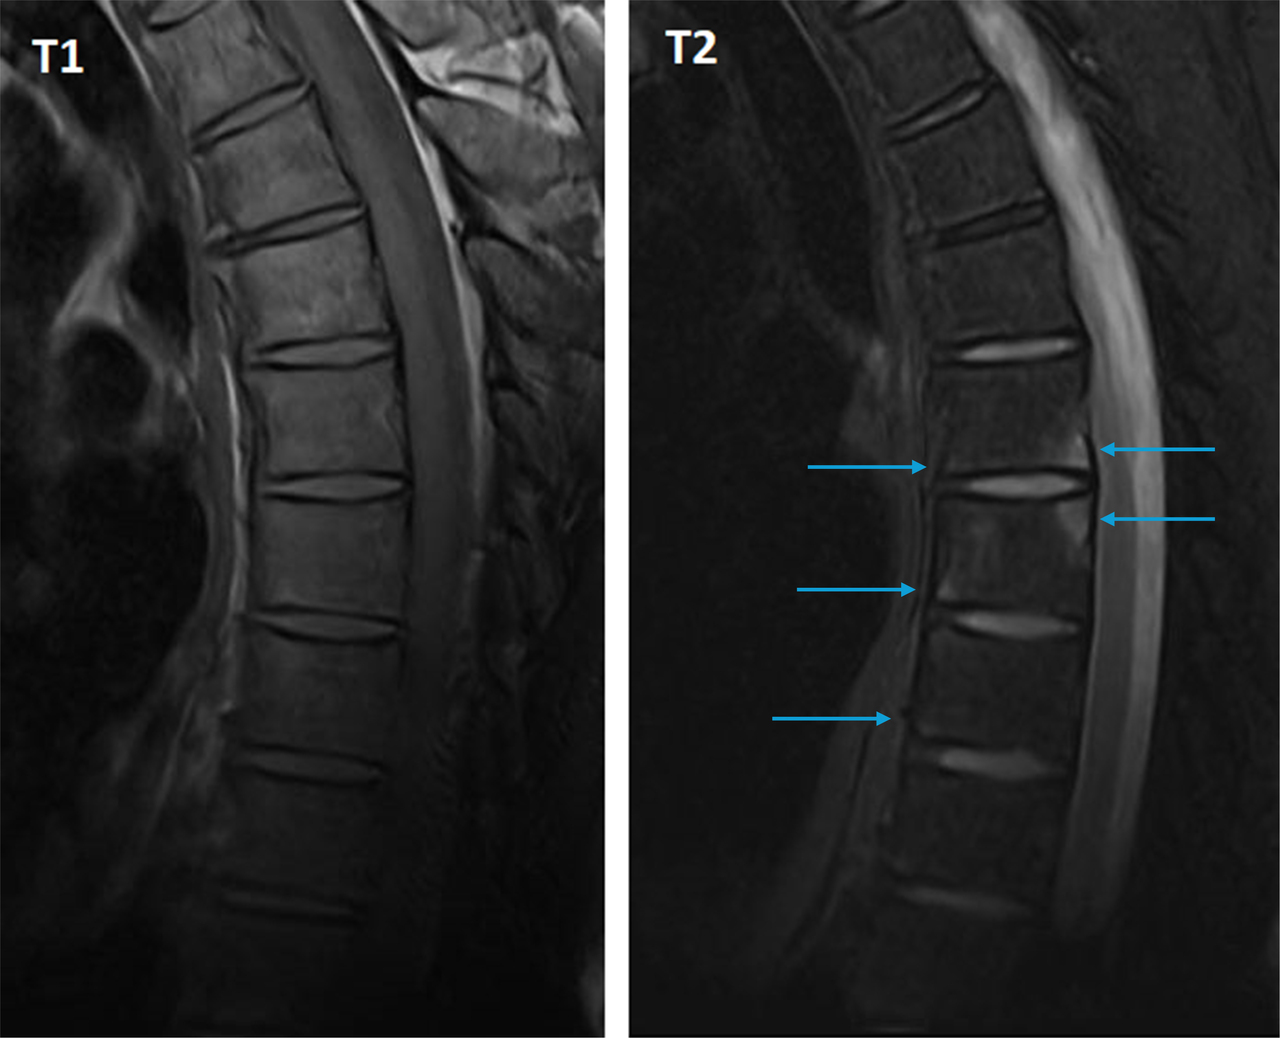

La vertèbre T6 montre deux coins inflammatoires : antéro-inférieur et postéro-supérieur.

L’IRM rachidienne montre de nombreux coins inflammatoires en hypersignal T2, qui témoignent d’une atteinte enthésitique au rachis. On les distingue des coins « graisseux » qui apparaissent en hypersignal T1 et en hypersignal T2 ou iso-signal sur les séquences avec suppression du signal de la graisse.

Figure 3 (Salomé Abdellaoui, La Revue du Praticien)